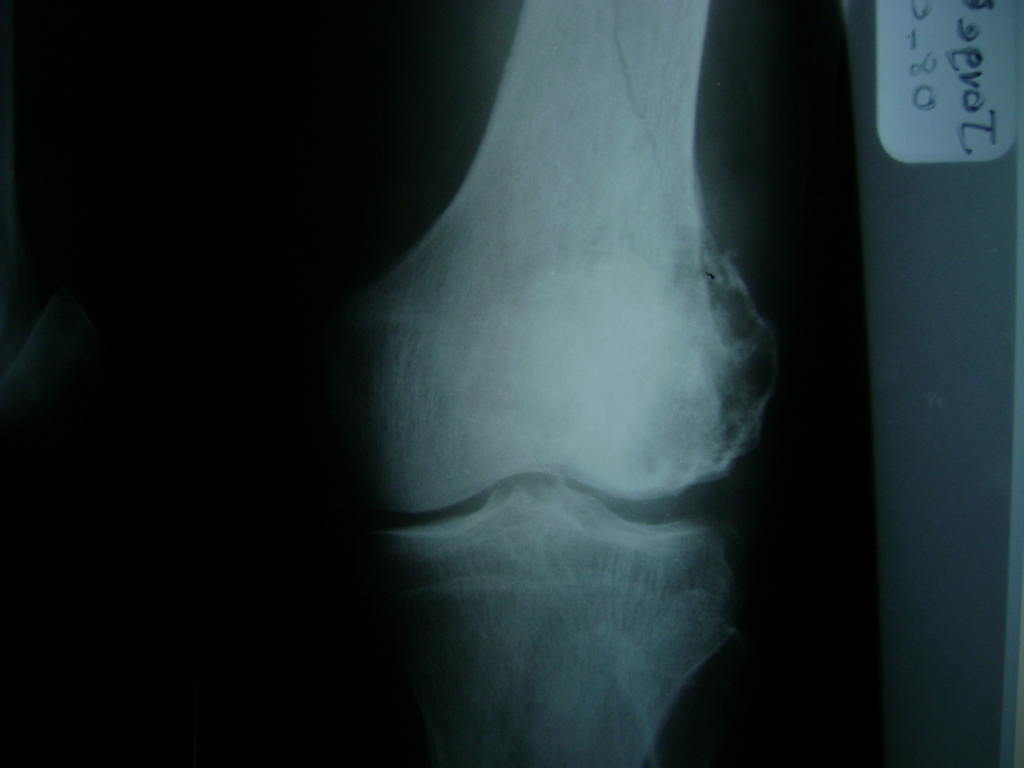

Fémur - Rodilla

La artroscopia de rodilla es un cirugía en el cual la estructura interna de la articulación es examinada ya sea para realizar un diagnostico o para realizar un tratamiento, este procedimiento se realiza utilizando un instrumento parecido a un pequeño tubo llamado artroscopio.